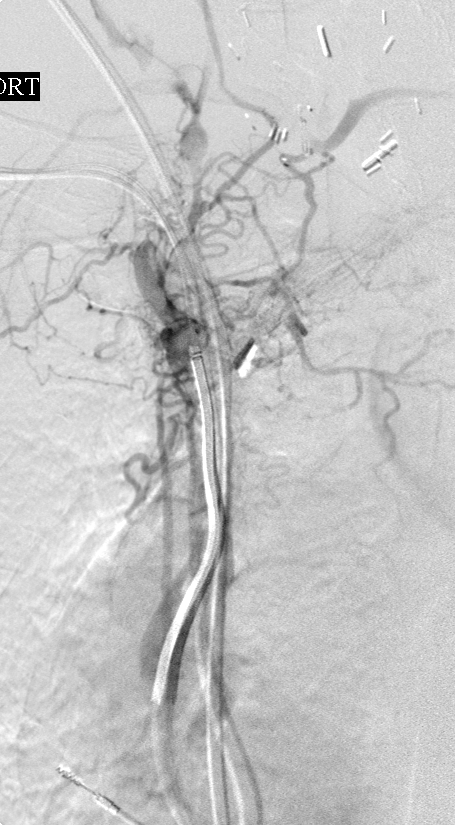

Terminal central venogram through the REJV: A guidewire has been passed through the recanalized vein into the IVC.